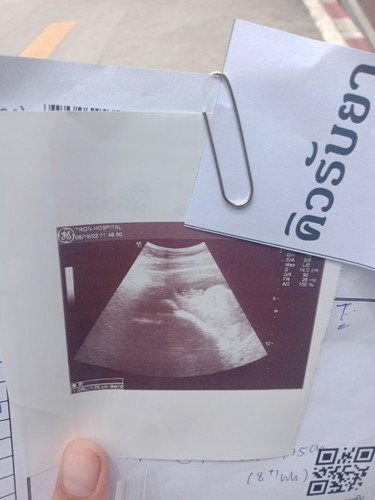

มาแล้วจ้าเจอหัวใจ💓แล้วตรวจเมื่อวันที่1เจอแต่ถุงวันนี้หมอนัดซ้ำอีกวันนี้เจอตัวเด็กแล้วหัวใจด้วยครั้ง

แรกที่เห้นน้ำตาแทบแจกเลยจ้าแม่8w4d